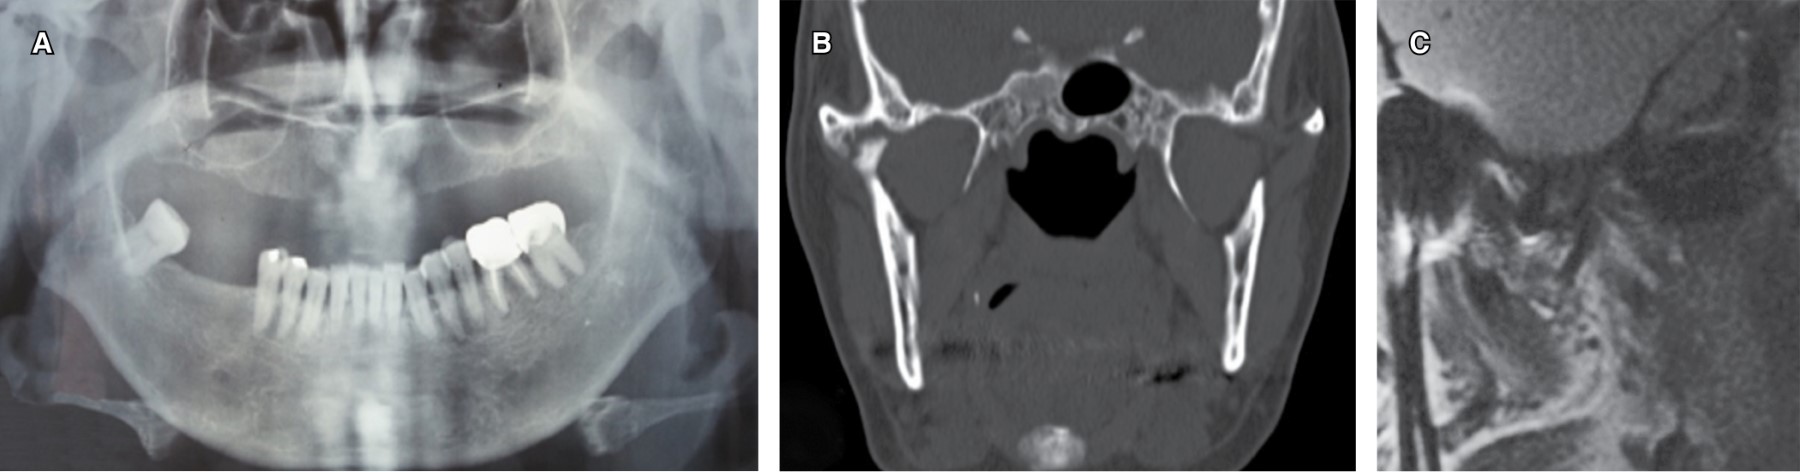

Se trató de una mujer de 60 años, la cual inició su padecimiento en octubre del 2014. Refiere antecedentes de una artroplastia de ATM izquierda en el 2005 y de la ATM derecha en el en el 2012. La paciente refirió dolor intenso de tipo punzante en la zona preauricular derecha durante la masticación, así como desviación mandibular a la apertura mínima, imposibilidad de adecuada alimentación y una limitación a la apertura de 13 mm (Figura 1). En la ortopantomografía (Figura 2A), tomografía y resonancia magnética se observa una anquilosis de ATM derecha tipo II, donde se identifica el cóndilo mandibular deformado con una fusión en el borde externo de la cavidad glenoidea (Figura 2 B y C). La ATM izquierda presenta el cóndilo deformado, pero sin presencia de adherencias de importancia. En un modelo estereolitográfico se diseñó la osteotomía, artroplastia y remodelación, así como la adaptación del acetábulo y prótesis condílea de stock o prefabricada (Biomet Microfixation)30 (Figura 3 A y B).

Figura 1

Figura 2